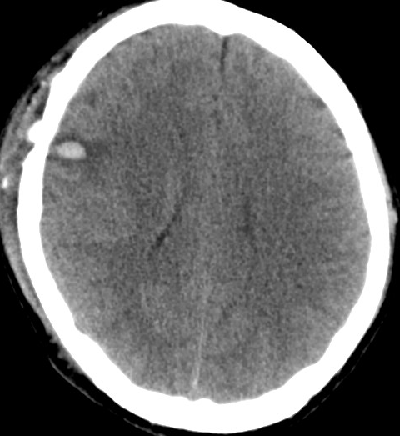

2014-9-29 CT

2014-10-5 CT